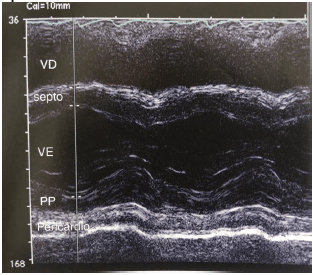

O traçado de modo M abaixo nos mostra um pericárdio espessado que se move com o epicárdio durante o ciclo cardíaco.